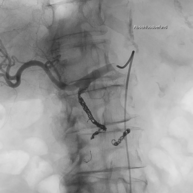

3. Stentimplantation – Einsetzen eines Stentes/ Gefäßstütze

Nach der Gefäßweitung kann durch Einrisse in den inneren Ablagerungen oder durch die Elastizität der Gefäßwand die Weitung nur ungenügend erfolgreich sein. Zur Stabilisierung des Befundes wird dann in diese Gefäßregion ein Stent eingesetzt. Dieser besteht aus einem feinen starren oder flexiblen Edelmetallgeflecht und kann auch mit Medikamenten gegen die Arteriosklerose oder zur Verhinderung der Bildung von Blutgerinnseln beschichtet sein.

Unter bestimmten Bedingungen, v.a. bei Verletzungen der Gefäße mit daraus resultierender Blutung oder lokalen Gefäßerweiterungen, werden Stents mit einer Ummantelung eingesetzt, die die Gefäßwand abdichten oder die Erweiterung überbrücken.